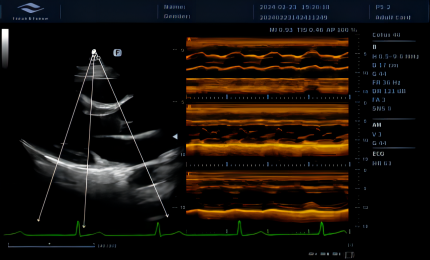

cw

Tryb CW wykorzystywany jest do analizy przepływów o wysokich prędkościach, szczególnie w diagnostyce kardiologicznej. Umożliwia dokładną ocenę zwężeń oraz niedomykalności, zapewniając wiarygodną analizę parametrów hemodynamicznych.

am

Zakrzywione AM

Krzywoliniowy tryb M (CAM) pozwala na jednoczesną analizę zależności przestrzennych i czasowych ruchu mięśnia sercowego. Umożliwia to dokładniejszą ocenę pracy serca oraz identyfikację zaburzeń kurczliwości w poszczególnych fazach cyklu.

am2

Tryb M umożliwia analizę ruchu struktur serca poprzez ustawienie linii pomiarowych pod dowolnym kątem. System pozwala na jednoczesne wykorzystanie kilku linii, co zwiększa dokładność pomiarów i umożliwia kompleksową ocenę pracy serca.